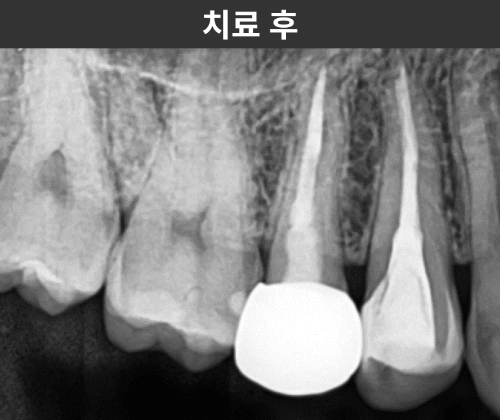

치료 과정

기존 크라운과 레진 코어를 제거하고

내부를 살펴본 결과, 예상치 못했던

충치와 오염된 조직이 발견되었습니다.

이처럼 겉보기엔 멀쩡해 보여도

내부에 문제가 있는 경우가 많기 때문에,

크라운 재치료 시에는 기존 재료를 모두 제거한 후

철저하게 청소하고 밀봉하는 과정이 중요합니다.

신경관은 두 개가 서로 연결되어 있는 구조였고,

이 부분을 모두 깨끗하게 치료한 후,

치아 벽이 절반 이상 손상된 부위에는

파이버 포스트를 이용해 보강을 했습니다.

이후 주변 치아 색상에 맞춰

지르코니아 크라운으로

자연스럽게 마무리했습니다.